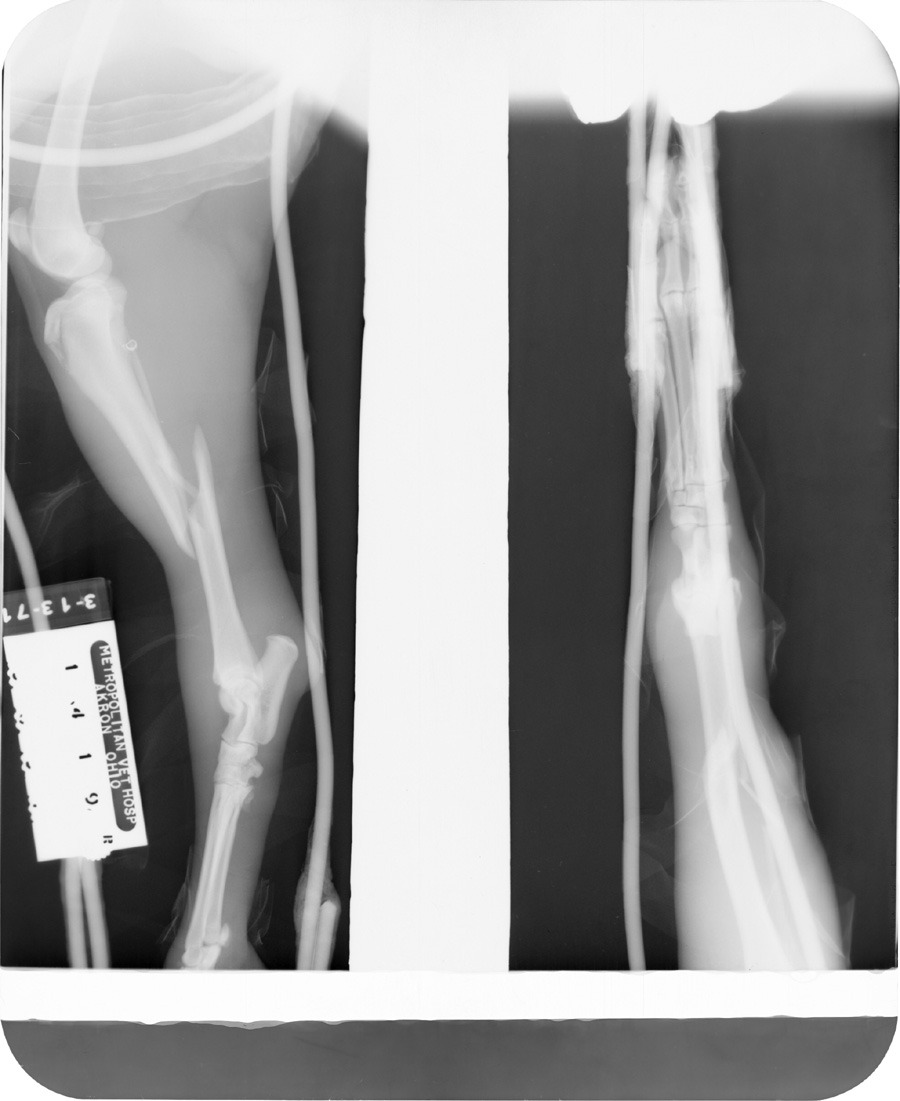

The very top edge of the film was neither developed nor fixed; therefore is still has emulsion on it. Clean area was fixed but not developed so al silver was removed from it. The rest of the film was developed and fixed.